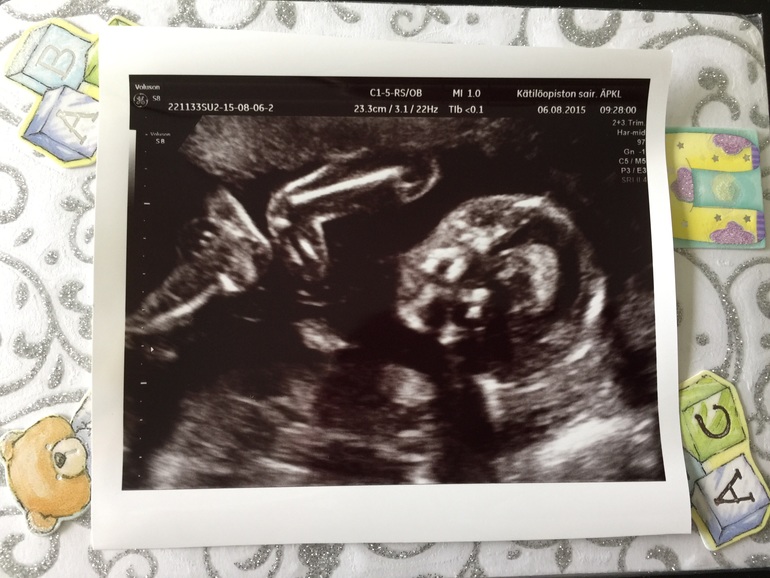

Ну и спустя 10 минут наш малыш показал свои прелести, честно это точно ни с чем не спутаешь! Нам так запечатлили хорошо, что сомнений не осталось)))

Вот фото:

Папа наш сидит улыбка до ушей, говорит "ну пипка то папкина, размеры что надо. Молодец мужик!"

А тут мы локоточками достали до коленок))) Муж сказал что это он нам свои мускулы показывает, мужик же)))

2) Срок сегодня 20 недель и 4 дня, вес сказали 346 грамм, по размерам сказала что соответствует сроку 20 недель и 2 дня. Это нормально что на пару дней отстает? Просто в 12 недель он догнал срок, а сейчас получается опять отстает. Переживать начала...

3) КТР не сказала. Это нормально? Написала в строке где указывают миллиметры 46,7. Ну это же не КТР, так я понимаю? Тогда что?